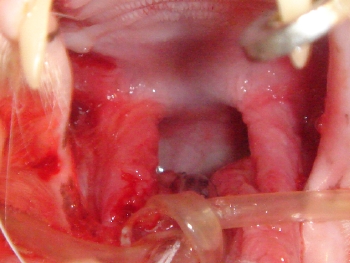

簡単に手術方法をご説明しますと、その部位の抜歯、殺菌を行い、滅菌下にて製剤を注入し、その後に縫合いたします。

症例:下顎のP4 - M1 - M2の重度歯周病による下顎骨折のリスク

*下の画像をご覧ください。青の矢印(②)で描写された幅が本来の下顎の幅です。つまり歯周病がなければ歯(M1)と下顎骨が一緒になって下顎の幅と考えられるわけです。しかし歯周病によって赤の矢印の幅分まで下顎が薄くなっております。特に①などに関しては骨折のリスクがあると考えてよいでしょう。

手術日のレントゲンです。赤い部分が骨充填した部位になります。

術後3ヶ月目の写真です。青の矢印で描出されているように下顎が再生されております。